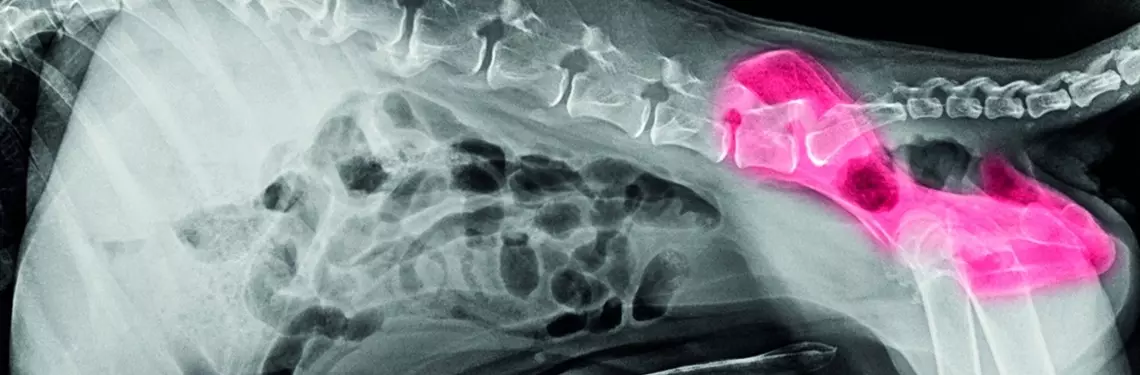

HD

Obciążone genetycznie szczenięta rodzą się z prawidłowymi stawami, a niestabilność prowadząca do dysplazji rozwija się u nich stopniowo. Pierwsze objawy, takie jak kulawizna, trudności w podnoszeniu się, ograniczone odwodzenie kończyn czy charakterystyczny chód (tzw. królicze kicanie), pojawiają się od około 6. miesiąca życia i zazwyczaj mają charakter ostry. Jest to okres najszybszego wzrostu zwierzęcia, za którym poniekąd nie nadąża siła mięśni i więzadeł, których zadaniem jest stabilizacja stawów. Dlatego też do ras predysponowanych należą przede wszystkim rasy duże i olbrzymie. Dalsza ewolucja objawów przypomina postępujące zwyrodnienie stawów, do którego zresztą prowadzi.

Patogeneza schorzenia polega na rozluźnieniu więzadeł i torebki stawowej otaczających stawy, co prowadzi...